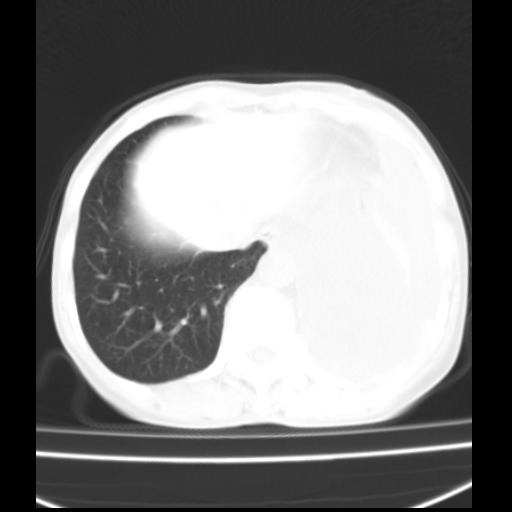

以下是引用随光逐影在2010-3-24 19:15:00的发言:[br]结合病史,考虑双肺及纵隔淋巴结多发转移、左侧胸膜转移并左侧大量胸水,左下肺膨胀不全。

以下是引用zxl51642在2010-3-24 18:49:00的发言:[br]结合乳腺癌术后病史,考虑双肺及纵隔淋巴结多发转移、左侧胸膜转移并左侧大量胸水、左下肺膨胀不全。